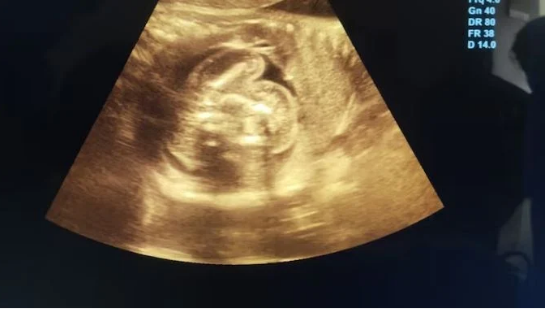

بدأت القصة عندما لاحظ والدا الطفلة انتفاخ بطنها وصعوبة فى الرضاعة مع عصبية مفرطة، دفعتهم هذه الأعراض إلى طلب المساعدة الطبية، لتكشف الفحوصات عن مفاجأة مذهلة: جنينان غير مكتملين محاطان بكيس واحد داخل بطن الطفلة.

يحدث “الجنين داخل الجنين” فى المراحل المبكرة من الحمل، حين يحيط أحد التوائم بالآخر ويُحاصر داخله، وهذه الأجنة لا يمكنها النمو بشكل مستقل، وتتحول إلى كتل مشوهة من الأنسجة، بحسب indiatoday، وأوضح الأطباء أن هذه الحالة ليست سرطانية ولا تتصرف مثل الأورام، ما يعنى أن استئصالها يُنهى المشكلة تماما ويجعل تكرارها أمرا شبه مستحيل.